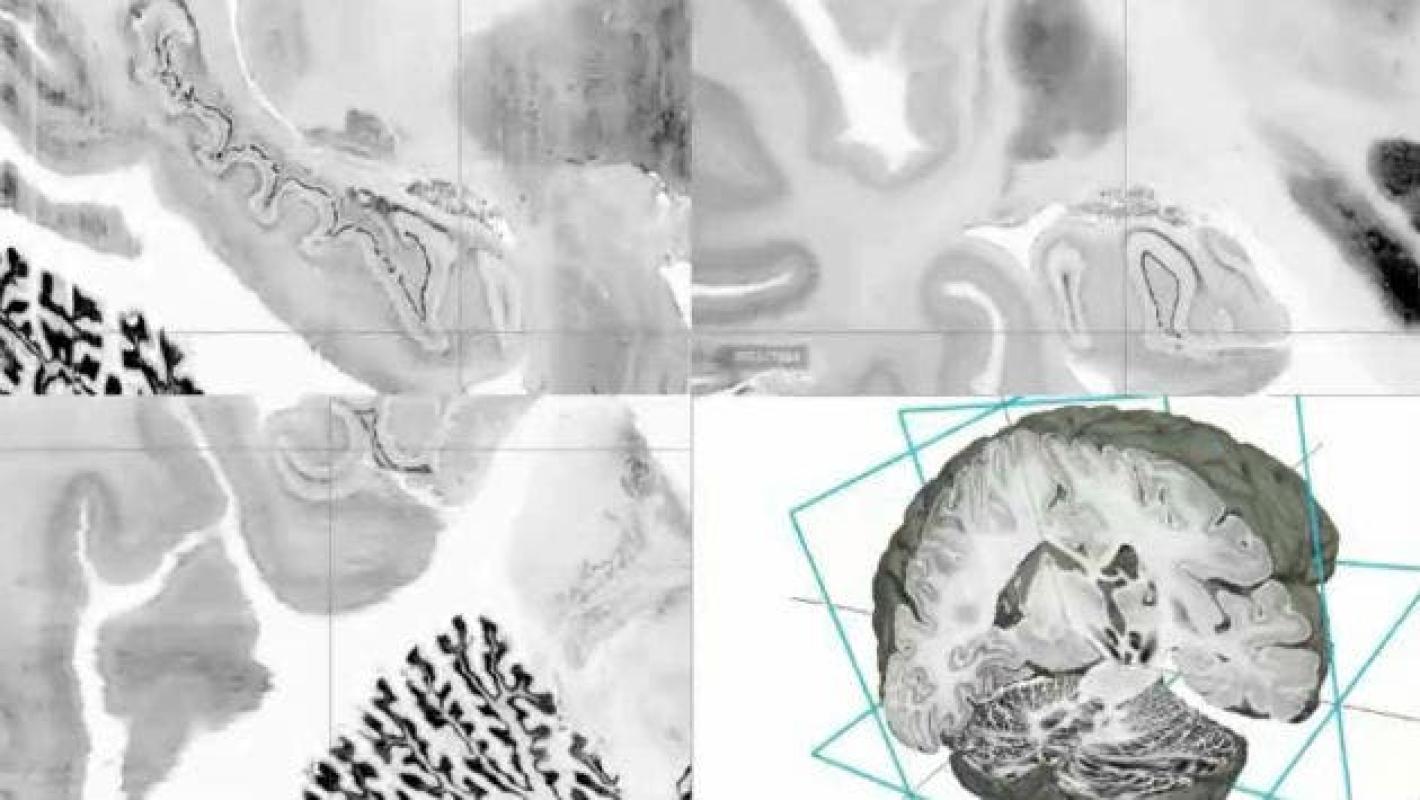

Científicos de la universidad de Harvard confirman que por primera vez en el mundo se lleva a cabo con éxito un experimento de telepatía, esto luego de que enviaran un "mensaje mental" de una persona a otra, las cuales estaban separadas por 4.000 kilómetros de distancia.

Según el Daily Mail, la primera persona debía pensar en una palabra y pese a que el sujeto que recibió el mensaje no podía comprender la palabra en sí, se registraron destellos de luz en su cerebro, los cuales se correspondían con el momento exacto en que el emisor pensaba la palabra.

Según los expertos a cargo del proyecto, esto muestra que "la tecnología se puede utilizar para transmitir información desde el cerebro de una persona a otra".

Giulio Ruffini, físico teórico y co-autor de la investigación, dijo: "estamos utilizando la tecnología para interactuar electromagnéticamente con el cerebro" y agregó que "es una especie de realización tecnológica del sueño de la telepatía, pero definitivamente no es mágico".

Por su parte, el profesor de neurología de la Universidad de Harvard y también co-autor de la investigación, Álvaro Pascual-Leone, señaló que querían ver si podían usar "vías existentes 'para saber si' uno podría comunicarse directamente entre dos personas mediante la lectura de la actividad cerebral de una persona y la inyección de la actividad cerebral en la segunda persona".